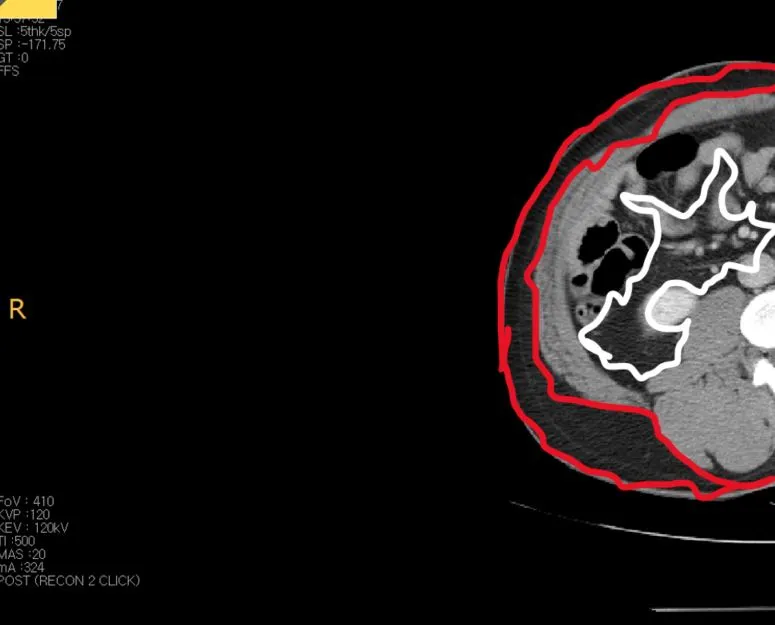

복부CT2.JPG 빨간 부분은 피하지방, 하얀 부분은 내장 지방

위의 CT 우측 반을 확대해서 표시를 해봤습니다. 하얀색으로 테두리 쳐진, 배 근육 안에 존재하는 지방들이 내장지방이고 바깥에 빨간색으로 테두리 쳐진 부분이 피하지방입니다. 사실 저는 살이 찔 때마다 피하지방보다는 내장지방이 걱정이었는데, 이번에 사진을 찍고 보니 등에 있는 살이 이렇게 많은 줄 처음 알았습니다. 저는 피하지방은 별로 없고 내장지방이 문제인 것으로 알고 있었거든요.